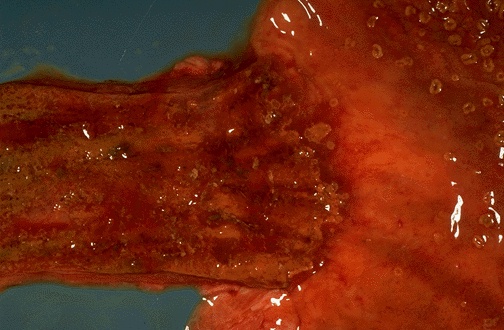

This is Candida esophagitis. Tan-yellow plaques are seen in the lower esophagus, along with mucosal hyperemia. The same lesions are also seen at the upper right in the stomach.